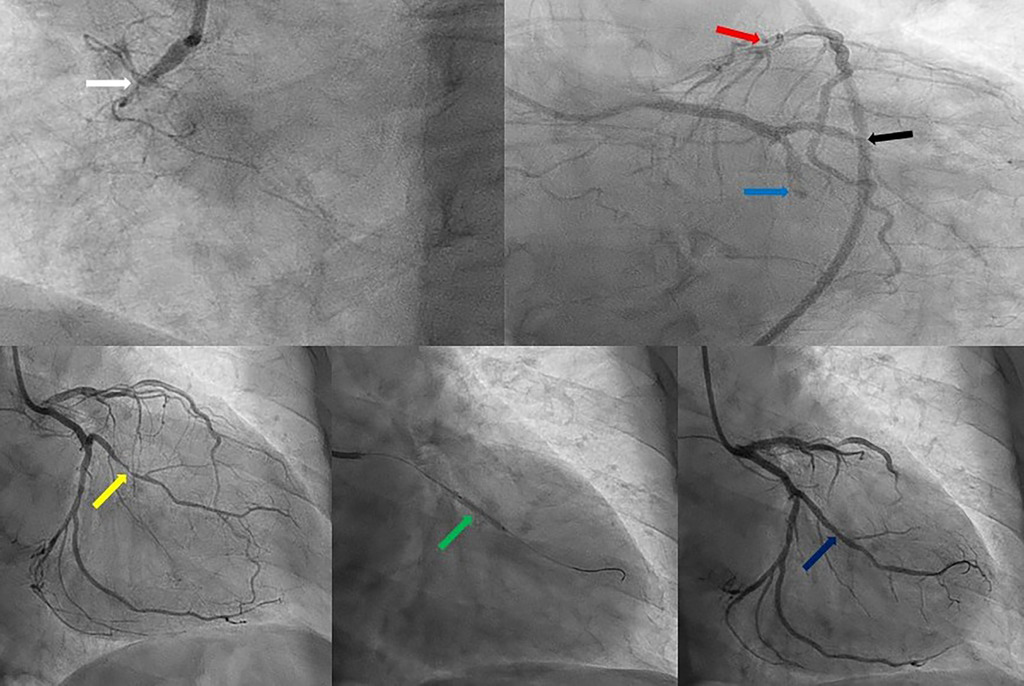

Через тривалість симптомів тромболізис не проводили. Було розпочато подвійну антитромбоцитарну терапію. Через 2 години після госпіталізації проведено коронарну ангіографію, яка виявила тяжке ураження кількох судин, у тому числі хронічну оклюзію правої коронарної артерії та субтотальні стенози OM1 і OM2.

На другий день проведено ЧКВ із імплантацією стента в OM1, OM2 реваскуляризувалася спонтанно.